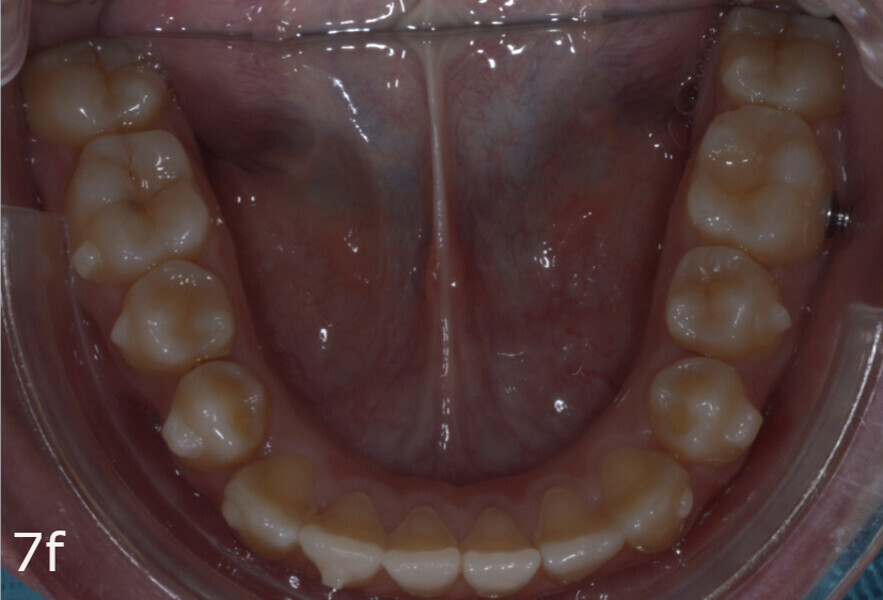

The 23-year-old dolichofacial female patient complained of not being able to chew properly. Facial examination showed a convex profile, an enlarged lower facial height, and a skeletal Class III malocclusion (Figs. 1–3). Intra-oral examination revealed an Angle Class III right subdivision malocclusion, anterior open bite, no overjet and a maxillary dental midline deviated about 3 mm to the right compared with the mandibular dental midline (Fig. 4). The panoramic radiograph confirmed previous extraction of the maxillary right first premolar and the presence of all four third molars (Figs. 5 & 6).

The treatment objectives included closing the anterior open bite, achieving a bilateral Angle Class I relationship and a proper overjet and overbite, correcting the midline discrepancies, and achieving a profile harmonisation. The treatment plan consisted of orthodontic camouflage treatment with asymmetric distalisation in three of the four quadrants using Invisalign aligners (Align Technology) and third molar extraction. The Invisalign Comprehensive package was chosen, and 63 pairs of aligners were used (Figs. 7–10). Each aligner was worn for 20 hours a day for one week each. The use of Class III elastics on both sides was indicated. Afterwards, ten refinement aligners were needed to improve the interdigitation on the right side (Figs. 11 & 12).

The total treatment time was 15 months. An Angle Class I relationship was established along with adequate anterior and canine guidance, establishing a functional occlusion. This not only ensures optimal masticatory function but also protects the teeth and the temporomandibular joint from excessive force. Maxillary and mandibular fixed retention were installed at the end of the treatment (Figs. 13–19).